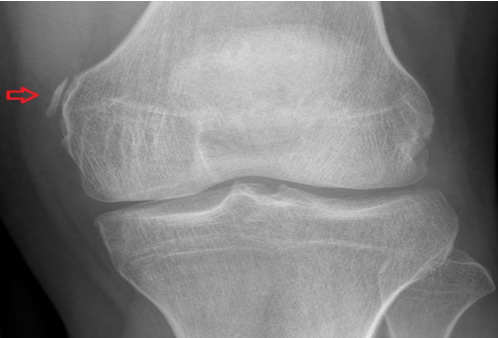

For acute knee injuries, an MRI is extremely helpful. An MRI can provide information about severity (complete vs. partial rupture) and location (avulsion vs. mid-substance tear). Of course, an MRI will also pick up associated injuries. For chronic conditions, it may be helpful to employ an MRI if and only if the anticipated results of the test will dictate management (Figure 4).

Figure 4: An MRI showing a high grade MCL tear proximally (red arrow). The yellow arrow points to intact ligament distally.